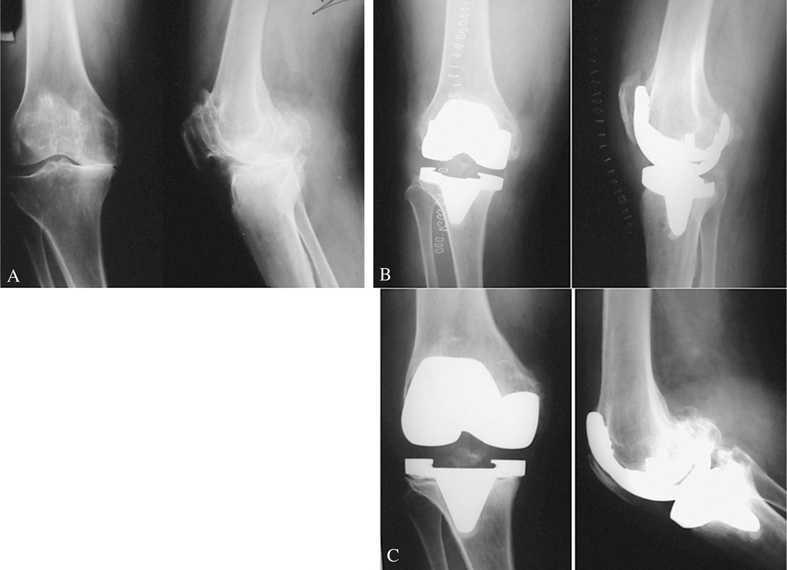

Con respecto al estado de satisfacción personal del paciente, obtuvimos un 78,2% de excelentes y buenos resultados (72 casos), (fig. 8) y tan sólo un 9,8% de malos resultados (7 casos), siendo estos los primeros que se implantaron, por lo que podemos atribuirlo a la curva de aprendizaje de toda intervención. Este resultado nos da una idea del excelente grado de aceptación de los pacientes con este modelo protésico.

Figura 8.(A) Mujer de 58 años (30/20 puntos). (B) Resultado excelente a los 8 años (90/70 puntos). (C) Varón de 60 años (52/30 puntos). (D) Resultado excelente a los 4 años (88/75 puntos).